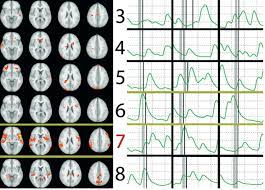

Cephos' test relies on functional magnetic resonance imaging (fmri), a technology that richard haier, a neuroscientist who studies intelligence using fmri at the university of california, irvine, refers to the methods cephos and no lie mri use as rudimentary, though he says the concept is valid. An fmri reveals active regions of the brain by tracking blood flow. Is there a part of the brain which is active when telling lies versus the truth? Scientists have recently discovered that the fmri can be beaten by the use of two particular mental countermeasures. This technique relies on the fact that cerebral blood flow and neuronal activation are coupled. Now a court case could decide whether fmris are the next lie detectors. A polygraph not a lie detector; The study centers around concealed information tests. To overcome this problem, researchers moved to methods that look directly at brain activation using fmri. Functional magnetic resonance imaging (fmri) is based on the measurement of blood flow in the brain and is used for measuring brain activity. A polygraph detects physiological expressions associated with lying in some people, such as a racing heart and sweaty fingers. Fmris are connected to specialized software able to not only. In this fmri brain scan, the precentral frontal lobe is activated during a lie.

Can Fmri Be Used As A Lie Detector - Fmris are connected to specialized software able to not only.. Until additional research is done, fmri can be used as a lie detector to help with the investigation, but it should not be used in court because it has limitations, it might not be reliable, and. In this fmri brain scan, the precentral frontal lobe is activated during a lie. Currently, fmri scans for detecting concealed knowledge and lies are not reliably better than using measures such as skin conductance, like sweating, he says. A polygraph detects physiological expressions associated with lying in some people, such as a racing heart and sweaty fingers. It's a standard tool for studying the brain, but research into the procedure is too cumbersome to be used so casually, george says.